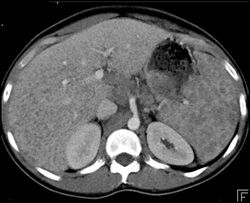

Normal Splenic Enhancement